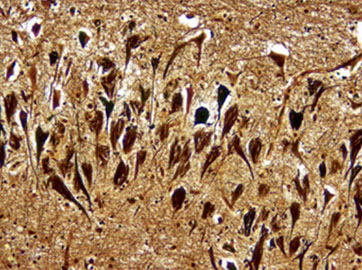

Inflammation (blue arrow) and dead red neurons (yellow)

Reactions of neurons to injury, ependymal cells: granular ependymitis; subependymal glial nodules; general rxn of ependyma to injury is cell loss w/o regeneration; prolif of subependymal glia can protrude into ventricle

Microglia, CD68

Reactions of neurons to injury, Microglia: neuonophagia. Microglia aggregates around dying neurons; seen in viral infx